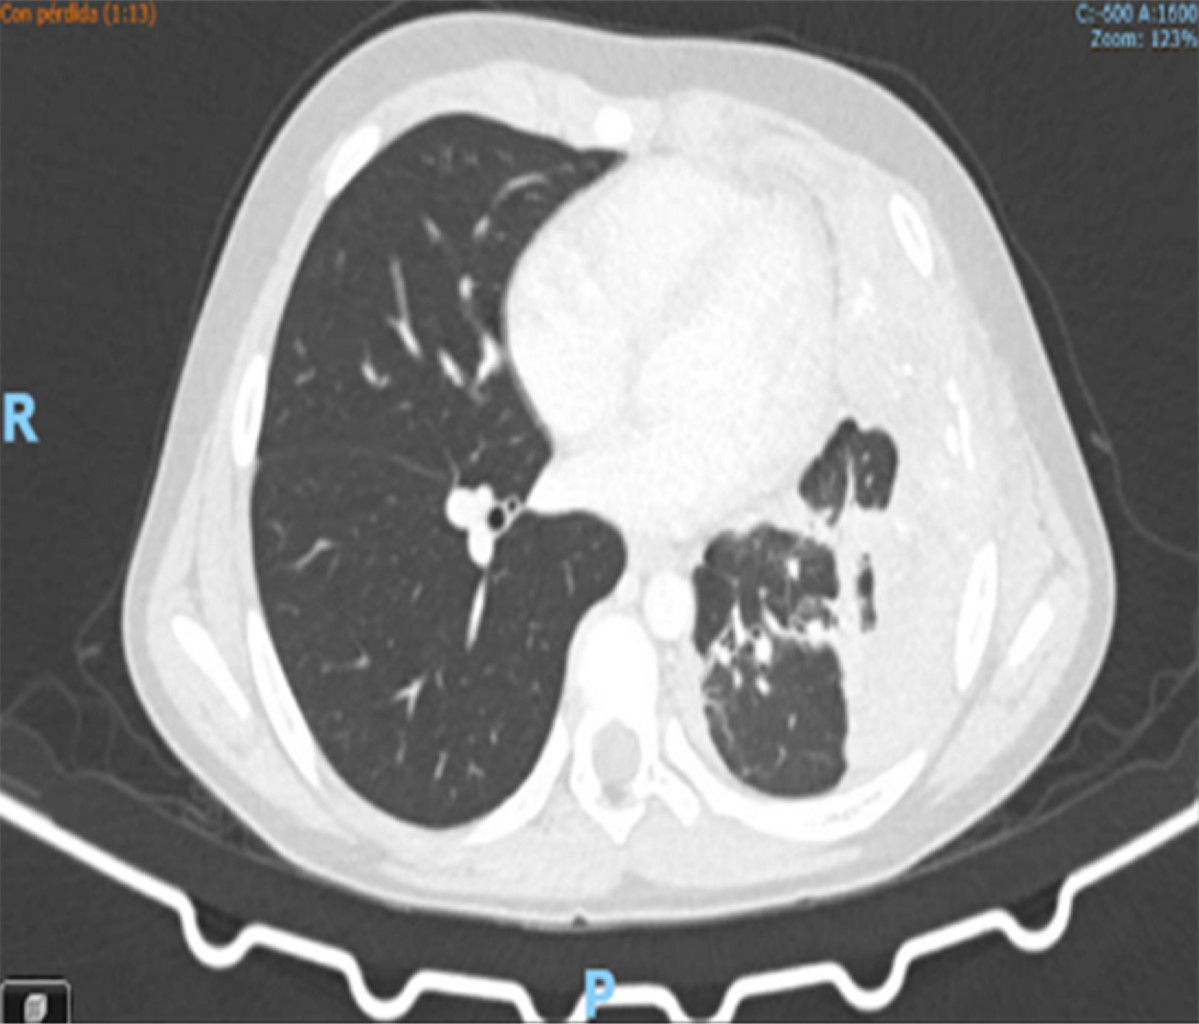

Masculino de siete años de edad, 30 kg de peso y 132 cm de talla, con diagnóstico de sarcoma de Ewing pleural izquierdo con compromiso de arcos costales 5, 6 y 7 izquierdos, con compromiso pleural y pericárdico, sin otros antecedentes de interés. Había recibido quimioterapia sistémica. El paciente ingresa el 01/10/2022 a urgencias por dolor de tipo pleurítico, sin asociarse a síntomas respiratorios. La tomografía axial computarizada (TAC) de tórax evidencia neoplasia infiltrativa de la pared del hemitórax izquierdo con extensión al hemidiafragma ipsilateral, pericardio, pleura parietal y visceral (Figura 1). En la resonancia magnética de tórax se encontraron nódulos aislados pleurales posteriores apicales izquierdos en relación con compromiso metastásico pulmonar. Desde el punto de vista oncológico, se determinó progresión de la enfermedad; por dolor severo del paciente, se consideró realizar neurólisis del plano del músculo erector de la espina, para lo cual se mantuvo al paciente con morfina 2 mg IV cada cuatro horas y rescates de 1 mg IV hasta cuatro en 24 horas en caso de dolor severo previo al procedimiento. A 10 días del ingreso a urgencias, el paciente fue llevado a manejo intervencionista del dolor; en decúbito prono, bajo previa asepsia y antisepsia, se realiza lavado quirúrgico, colocación de campos estériles, mediante guía ecográfica y fluoroscopía se identifican planos de apófisis espinosas torácicas (Figura 2), se situó central apófisis espinosa de T4, lateral a ella se identificó lámina y luego apófisis transversa con imagen en plano. Bajo anestesia general, se llevó la aguja a cuerpo de apófisis transversa y se colocó volumen de 20 cm3 en el plano del erector de la espina, identificando elevación del erector de la espina (Figura 3). No se presentaron complicaciones. Se realizó neurólisis unilateral del plano erector de la espina T4 izquierda con mezcla analgésica: 6 cm3 de alcohol al 99% + 4 cm3 de solución salina al 0.9% + 5 cm3 de bupivacaína al 0.5% sin epinefrina. Con adecuado control de dolor, posterior a procedimiento con FLACC (Face, Legs, Activity, Cry, Consolability) de 0, no requirió uso de rescate de opioides potentes, no presentó dolor incidental ni irruptivo y tuvo adecuado patrón de sueño. Posterior a esto, recibe radioterapia externa conformacional con intención paliativa. Dos días después del procedimiento, paciente con FLACC de 2 y al siguiente 0 con disminución del consumo analgésico. Por adecuada evolución clínica, se da egreso el 14/10/2022. Al mes control con adecuada evolución y FLACC de 0.

Figura 1